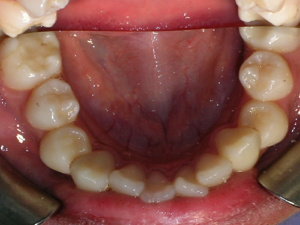

Here’s a young lady who presented with severe crowding. Often we think of crooked teeth as being limited to front teeth. Here one can see that back teeth can also get crowded. Braces were placed and select teeth were removed. Watch.

Look at the before and after of the second molar on the right side.